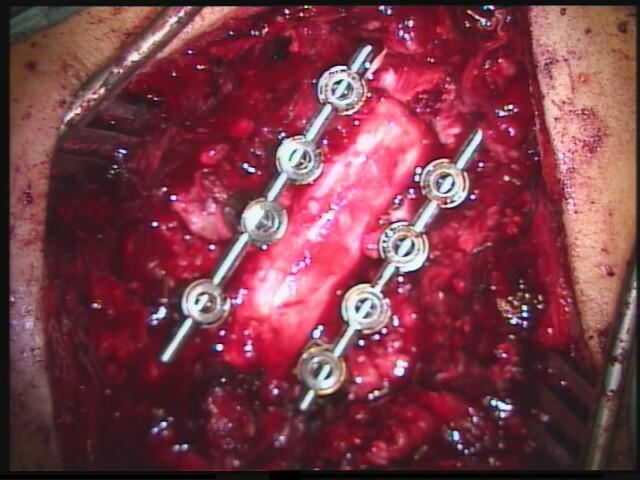

Versteifung der Halswirbelsäule von ´hinten´:

Bei einer lang gestreckten Verengungen des Rückenkanals muss das Rückenmark wieder genügend Platz bekommen. Dies gelingt in seltenen Fällen nur durch eine knöcherne Öffnung des Spinalkanals von hinten. Dazu ist eine Versteifung der Wirbel mit einem Schrauben-/Stangensystem erforderlich. Das ist in diesen Fällen die einzige Möglichkeit um einer Zunahme eines Rückenmarksschadens mit Querschnittssymptomen vorzubeugen. Diese Operation führe ich in Diez gemeinsam mit Prof. Schönmayr durch.